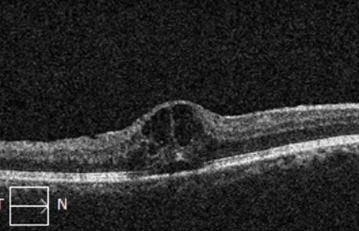

- Cystoid macular edema (CME)

- Edema means “swelling”

- Blood vessels damaged from the vein occlusion are leaky, and the fluid that leaks from these vessels accumulate in the retina

- The macula is the centermost part of the retina, which is responsible for much of high quality vision

- Swelling (edema) in the retina results in vision loss

- Optical coherence tomography (a scan to look for swelling in the retina (DME))